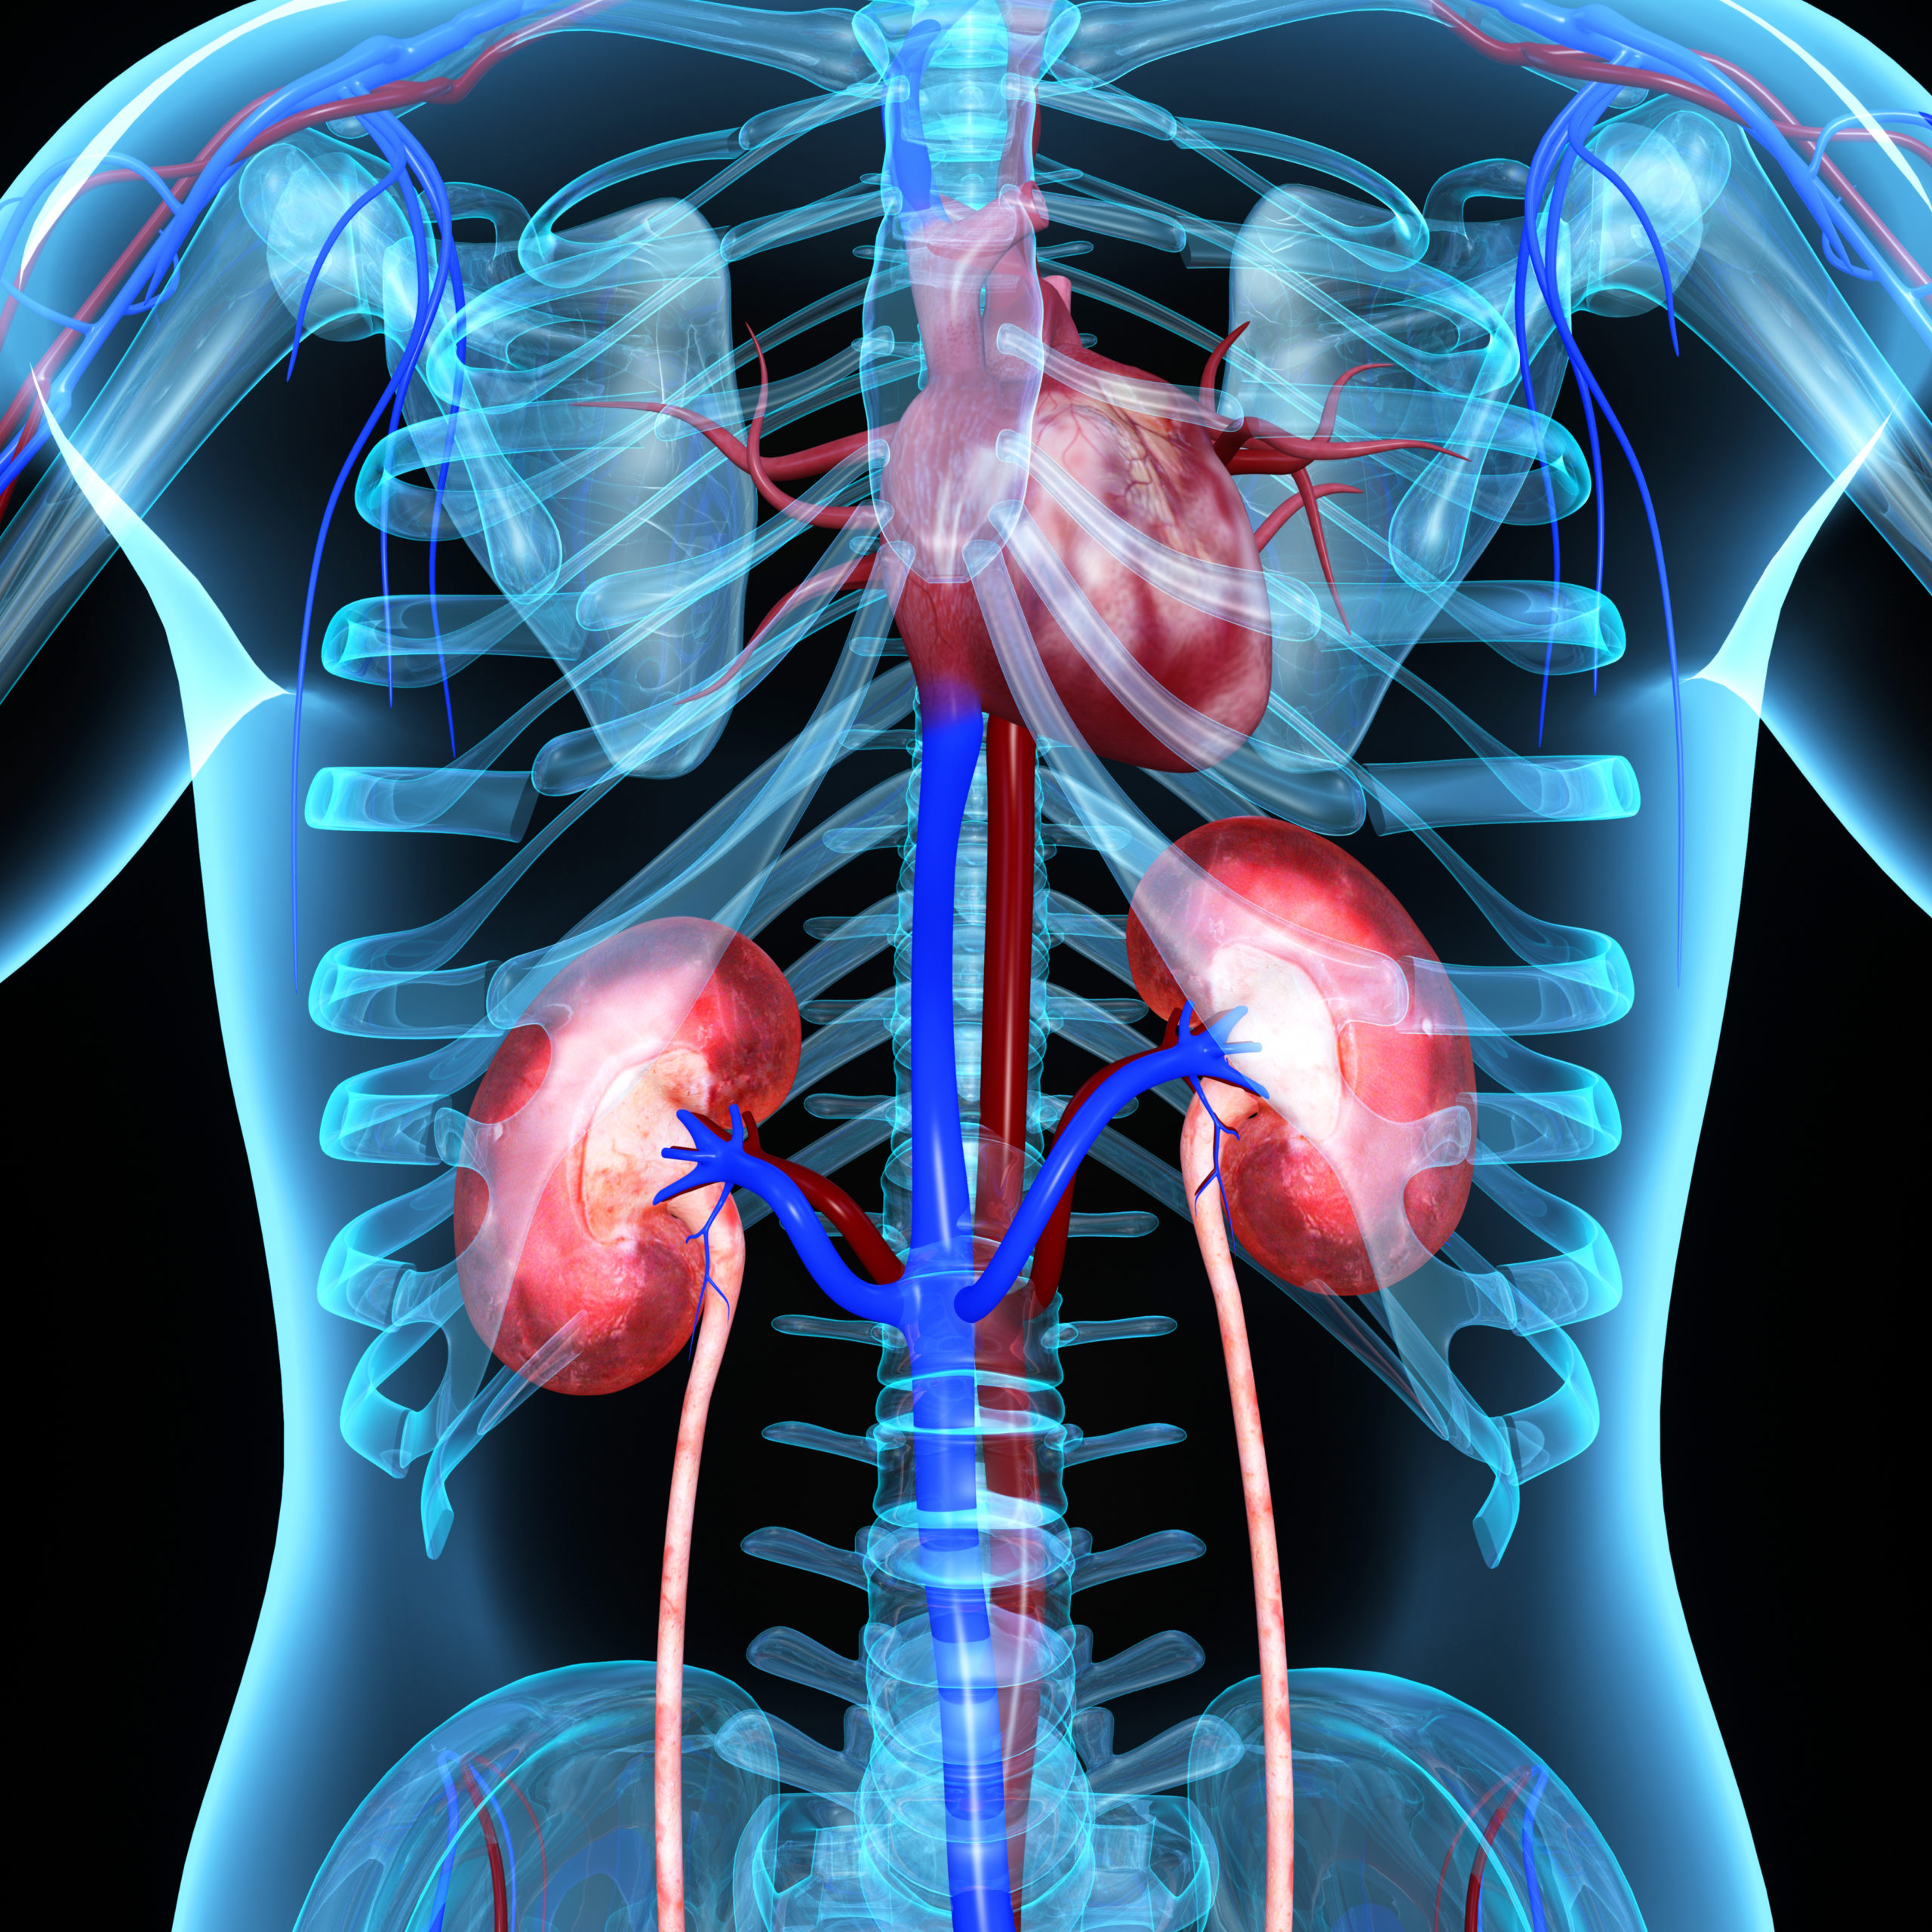

ความสัมพันธ์ของโรคไตกับโรคหัวใจ – Praram 9 Hospital รูปไอคอนหัวใจ PNG , ภาพตัดปะหัวใจ, ไอคอนหัวใจ PNG , ตัวแปลงไอคอนภาพ PNG …

โรคหลอดเลือดหัวใจ (Coronary artery disease) อาการ สาเหตุ การรักษา ฯลฯ หมอเอ็กโซติกอ่านฟิล์ม “การเอกซเรย์และ ECG ในกระต่ายหัวใจโต” – epofclinic